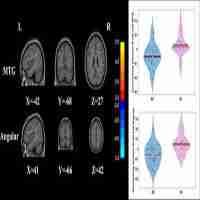

| Abstract | Objective: Clinically, it is very difficult to distinguish between major depressive disorder (MDD) and bipolar disorder (BD) in the period of depression. Increasing evidence shows that the insula is important in depression. We aimed to compare the resting-state functional connectivity (rsFC) of insular subregions in patients with MDD and BD in depressive episodes (BDD), who had never experienced manic or hypomanic episodes when they were scanned to identify biomarkers for the identification of two diseases. Method: We recruited 21 BDD patients, 40 MDD patients and 70 healthy controls (HC). Resting-state functional magnetic resonance imaging (rs-fMRI) was performed. BDD patients had never had manic or hypomanic episodes when they were scanned, and the diagnoses were determined by follow-up. We divided the insula into three parts including the ventral anterior insular cortex (v-AIN), dorsal anterior insular cortex (d-AIN) and posterior insula (PI). The insular-based rsFC was compared among the three groups, and an analysis of the correlation between the rsFC value and clinical scale was carried out. Results: BDD and MDD patients demonstrated decreased rsFC from the v-AIN to the left superior /middle frontal gyrus compared with the HC group. Versus MDD and HC groups, BDD patients exhibited decreased rsFC from the v-AIC to the area in the left orbital frontal gyrus and left superior temporal gyrus (included temporal pole), from the PI to the right lateral postcentral gyrus and from all three insular subregions to the somatosensory and motor cortex. Meanwhile, a correlation between the rsFC value of the PI-right lateral postcentral gyrus and anxiety score was observed in patients. Conclusion: BDD and MDD patients indicate similar decreases in insular connectivity in the dorsal lateral frontal regions, and BDD patients have specific decreased insular connectivity, especially in the somatosensory and motor cortex, which may be used as imaging evidence for clinical identification. |